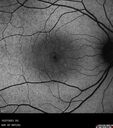

Albinism and Renal failure - Possible Hermansky-Pudlak Syndrome61 views65 year old female with foveal hypoplasia and renal failure since age 18. VA 20/40 OD, 20/63 OSDec 21, 2024